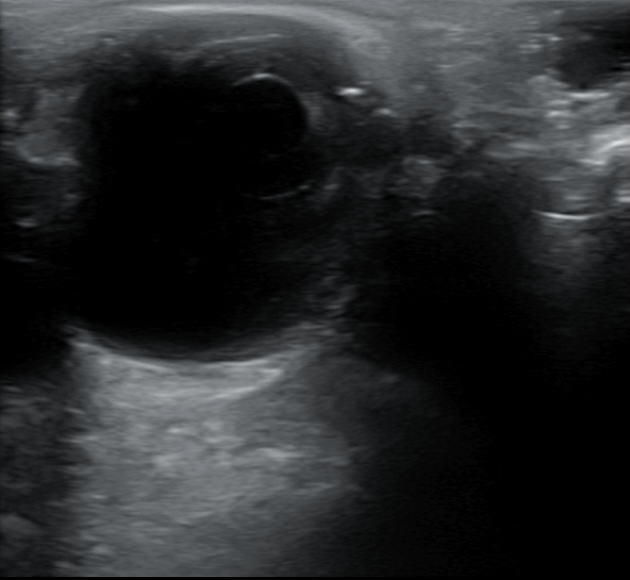

Hallazgos ecográficos

Se realiza ecografía donde se aprecia DVP en ojo derecho sin descartar hemovitreo y en campo superior y nasal una membrana más gruesa.

Se decide derivar al paciente al Servicio de Urgencias Hospitalarias para ser valorado por oftalmólogo y descartar posible desprendimiento de retina en ojo derecho. En el Servicio de Urgencias el paciente es valorado por oftálmologo de guardia y se confirma desgarro retiniano en herradura con hemovítreo.